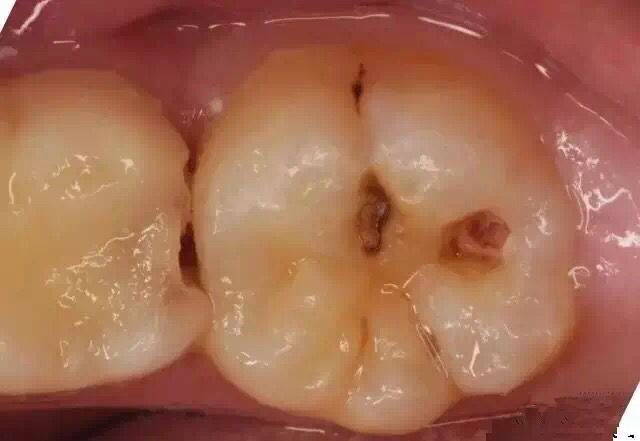

当我们牙上有小黑点时,您毫不在意地说:“没事的,没感觉。”

牙医说:“龋病是由以细菌为主的多因素导致的牙齿硬组织发生慢性进行性破坏的一种疾病。已经开始浅龋即牙釉质龋,需要做药物治疗或充填治疗。